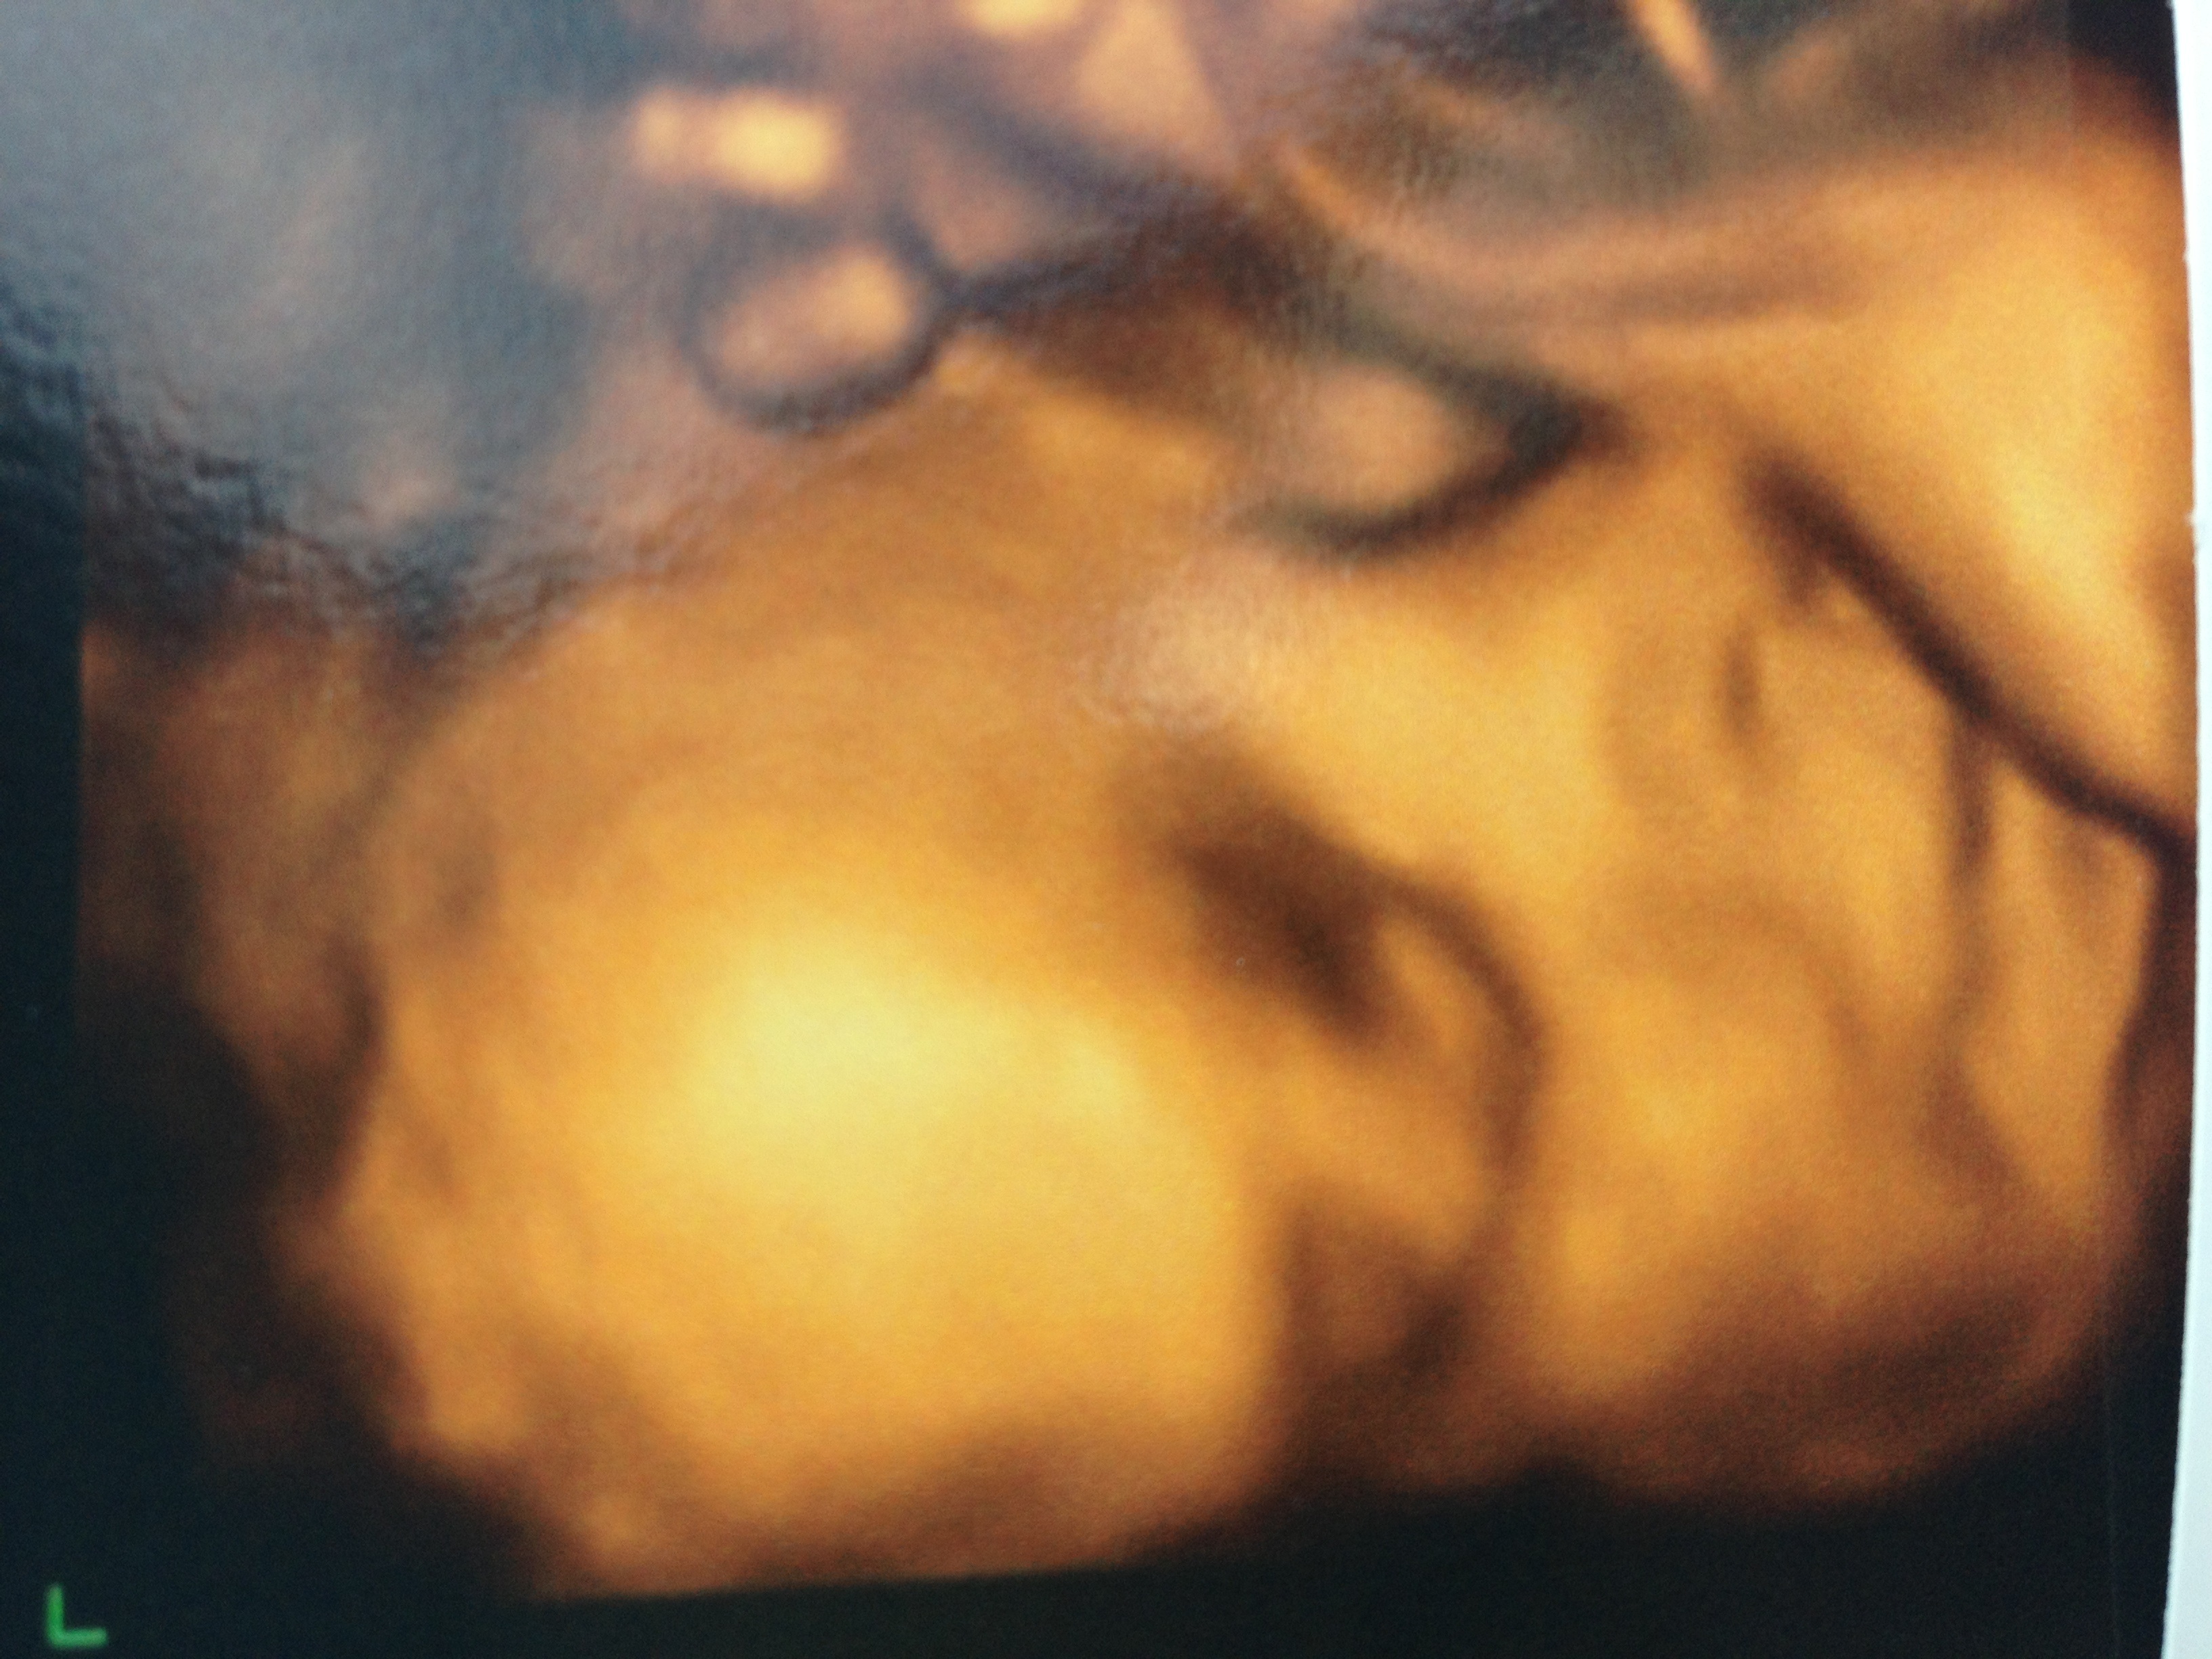

New to the site, would really love some predictions on my scan from 12+2! Have hopefully included two pics, both from the same scan.